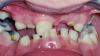

Конкурс на самого интересного больного проводят стоматологи России

Конкурс на самого интересного больного проводят стоматологи России vsekonkursy.ru

Мурмурище Мурмурище, 11 Февраля 2008

Уже шесть лет российские стоматологи соревнуются друг с другом, кому попался самый интересный клинический случай. Чистите зубы, если не хотите помочь вашему стоматологу выиграть конкурс. ...